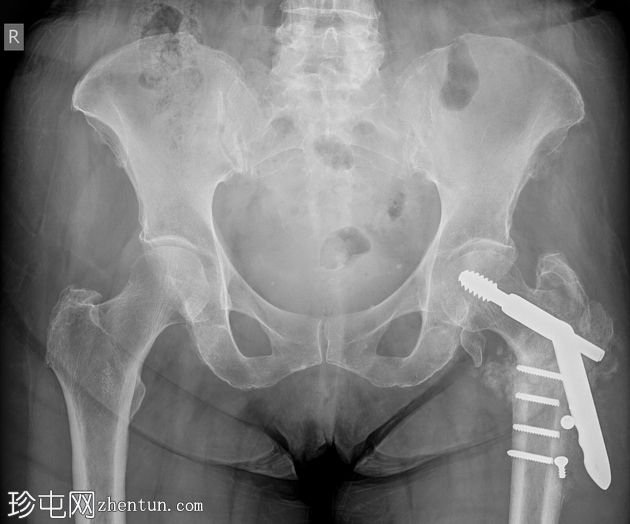

X线片

正位片

最下方三枚螺钉发生骨折,螺钉头移位。远端钢板松动。骨膜广泛钙化,股骨颈骨折仍清晰可见。

这是一个动力髋螺钉内固定失败的案例。该患者的具体原因尚不明确,但通常包括:骨质疏松、骨折类型/粉碎程度以及手术技术问题。